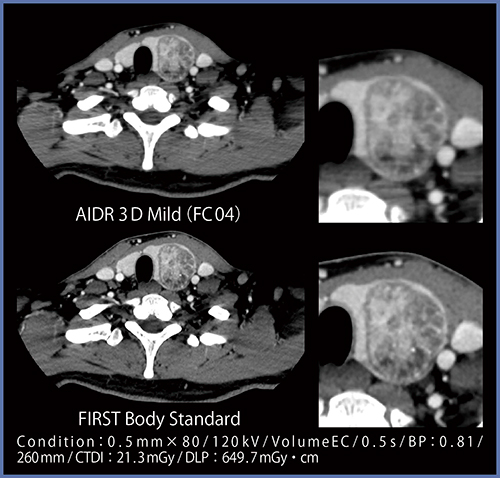

●症例7:甲状腺腫瘍

AIDR 3Dでは肩口の辺りにストリークアーチファクトが認められるが,FIRSTでは低減され,甲状腺左葉の腫瘍内部の構造が明瞭に描出されている(図9)。

図9 症例7:甲状腺腫瘍